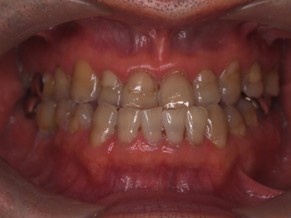

外科矯正治療・インプラント治療の症例紹介(三隅歯科クリニック)

| 主訴 | 20代女性 矯正治療希望。治療途中の歯もあるので治したい。左顎関節が痛い。 |

| 治療内容 | 矯正治療を行いました。 |

| 治療費 | 1,400,000円(税込み) |

| 治療期間 | 3年(矯正治療期間 2年半) |

| 治療回数 | 40回 |

| 想定されたリスク | 顎骨の変形があったので、全身麻酔下による外科処置が必要になり、身体的、精神的負担が増す可能性がありました。 清掃状況によっては矯正中にむし歯が発生するリスクがありました。 |